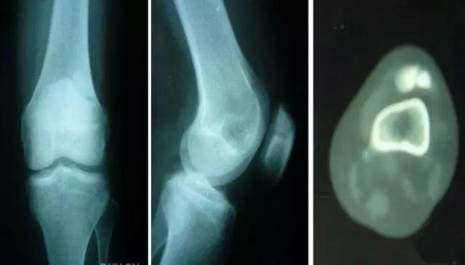

7 剥脱性骨软骨炎

关节内的骨软骨病,病因不明,关节软骨和软骨下骨变性和再钙化,最常见于股骨内髁,模糊的、定位不清的膝关节疼痛,有晨僵,反复的关节内积液(轻度)。如有游离体,可发生交锁症状。股四头肌萎缩,受累股骨髁关节软骨面压痛。

X线平片显示骨软骨病损或关节内游离体。如怀疑剥脱性骨软骨炎,摄片应包括前后位、后前隧道位、侧位和髌股关节切线位。